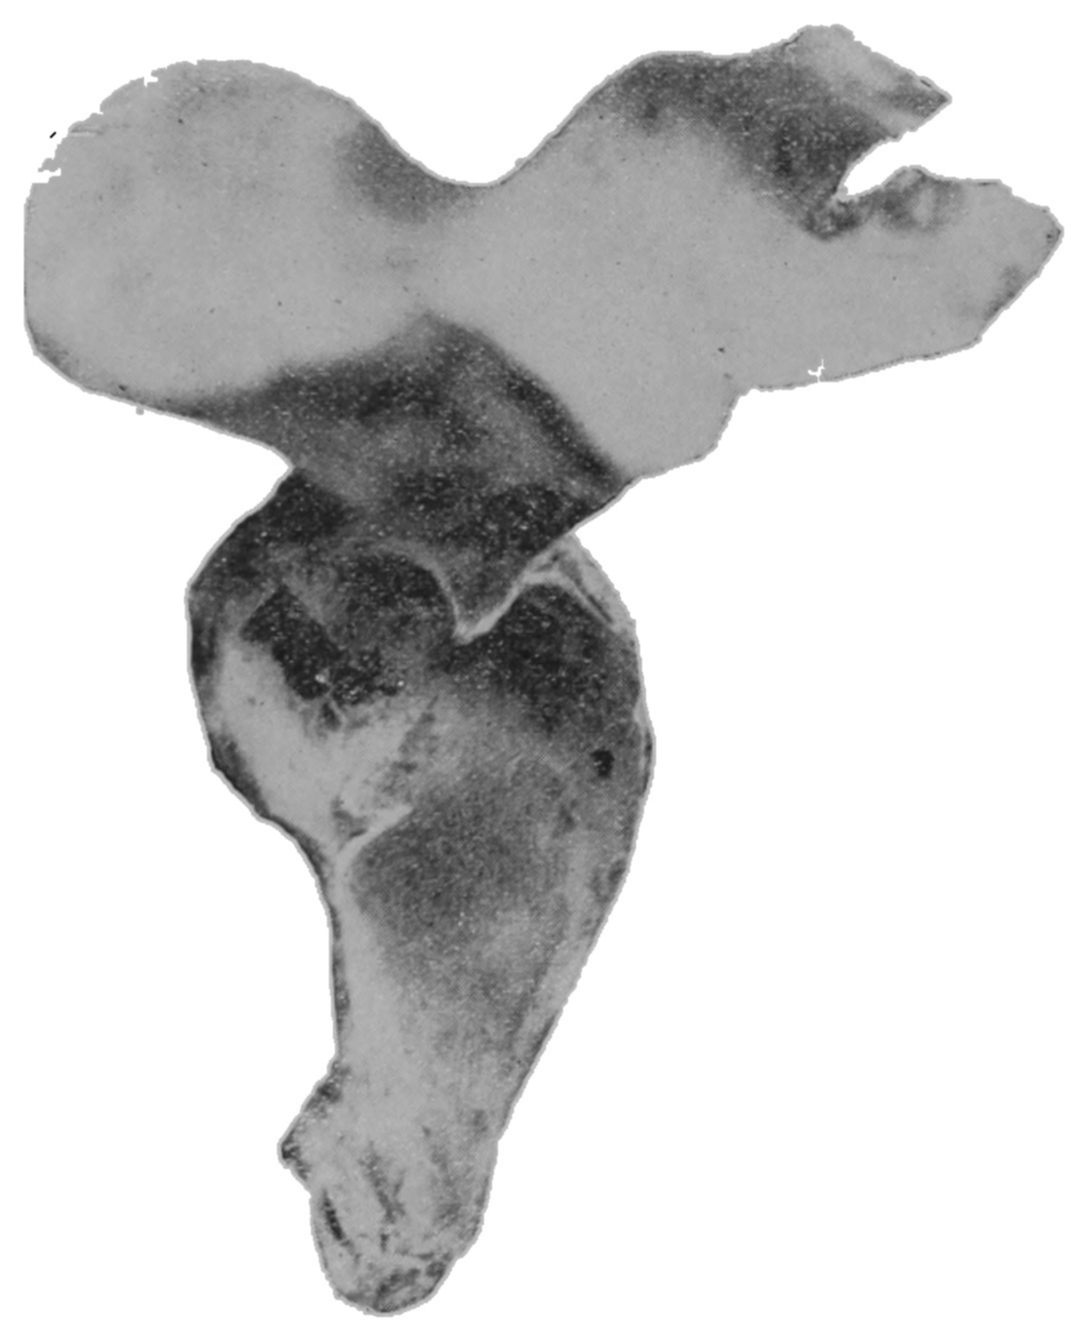

Fig. 19.—Drawing of specimen No. 281 in the Anatomical Museum of the Royal College of Surgeons, London. The dissection was made by Mr. William Pearson. The drawing shows in the lower part of the field the coccyx, in the upper part of the field the pubes.

Fig. 20.—Drawing of specimen No. 284 in the Anatomical Museum of the Royal College of Surgeons, London. The dissection was made by Mr. William Pearson. The drawing shows in the lower part of the field behind the rectum the coccyx, in the upper part of the field the pubes.

The fixed anal rectum begins at the levator ani and coccygeus muscles. The levator ani has its origin at the sides of the bodies of the pubic bones, the coccygeus at the spines of the ischii, and the levator ani has additional origin from the fascia and bony parts on a line between these two points. The fibers of these muscles are directed downward and inward to the fixed anal rectum; many fibers are blended into the contiguous structures of the pelvic floor. The coccygeolevator muscles may be compared to an opened slat-fan, the apex having its place at the anus, and its long border representing the line of origin of the muscles, Fig. 19. The ental sphincter ani muscle, situated a few lines below the levator ani, is made up of an aggregation of the fibers of the circular non-striated muscular intestinal coat, Fig. 20. The ectal sphincter ani striated muscle is situated immediately beneath the external skin. It serves the present occasion to describe the ectal sphincter of the male as a loop of muscle thrown about the terminal end of the rectum and hitched to the terminal bone of the coccyx, and in the female as a longer loop of muscle twisted upon itself so as to make a tandem-loop,[56] which, in the form of the figure eight (8), is thrown about the vagina and terminal end of the rectum.